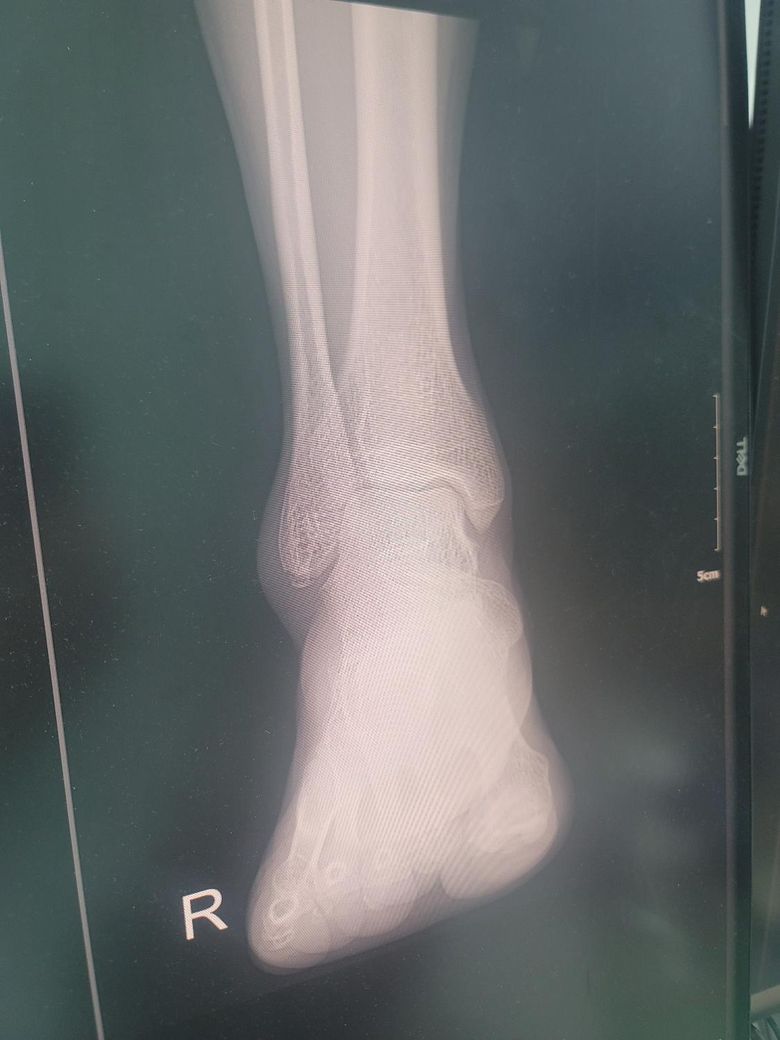

사진에서 보이는것 처럼 비골 아래쪽이 골절인데 본깁스만 몇주착용하고 치료가 가능할까요?

제공해주신 엑스레이 이미지를 보면 비골 원위부에 비교적 정렬이 유지된 단순 골절로 보이고 심한 어긋남이나관절면 침범은 없어 보입니다. 이 경우 수술 없이 어긋남이나 관절면 침범은 없어 보입니다.

이경우 수술 없이 본깁스나 보조기 착용만으로도 충분히 치료 가능한 경우가 많습니다. 보행 시 큰 통증이 없다면 의사의 지시에 따라 조심스레 보행 가능하고 일반적으로 4~6주 정도 고정 후 단계적 재활을 합니다!

일단 올려주신 엑스레이를 봐보면 비골 원위부 부분에 비교적 정렬이 유지되어 있는 단순 골절로 보이며 심한 어긋남이나 관절면의 침범은 없어 보여 수술적인 치료까지는 필요 없을 것으로 생각되며 회복이 잘 될 수 있도록 깁스나 혹은 보조기등을 잘 착용하시면 좋을 것으로 생각됩니다.